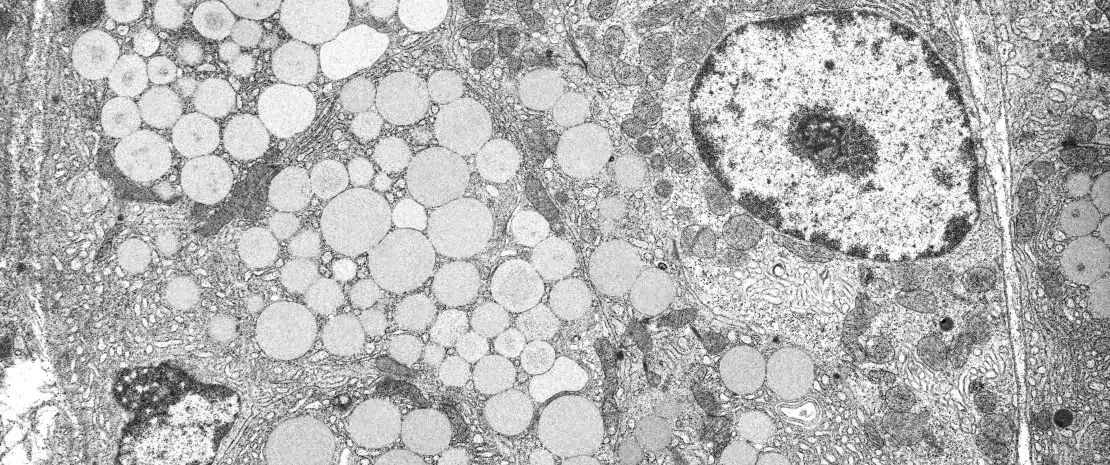

Proton pump inhibitors (PPIs), which are nowadays ones of the most widely used medicines even if about half of the prescriptions lack an evidence-based indication, have a central role in the treatment of peptic ulcer and gastro-oesophageal reflux disease. PPIs inhibit acid secretion from gastric parietal cells. PPI-induced hypochlorhydria may increase the risk of infections.

Mishiro et al. investigated the impact of 20 mg daily esomeprazole for 1 month on saliva, periodontal pocket fluid and fecal microbiota in 10 healthy volunteers.[1] Colonic microbiota contained the greatest number of species. Firmicutes, Bacteroidetes, Actinobacteria and Proteobacteria were the most abundant species in faeces, whereas Firmicutes, Proteobacteria, Bacteroidetes and Fusobacteria were the most common in saliva and periodontal pocket fluid. PPI caused a significant reduction in the diversity of salivary microbiota. Streptococci, which are predominantly found in the upper gastrointestinal tract, were increased in faeces and also in saliva and periodontal pocket after PPI treatment.[1]

Mailhe et al. examined the gastrointestinal microbiota composition of 6 patients who underwent gastroscopy and colonoscopy.[3] Samples were obtained from stomach, duodenum, ileum, and colon. Culturomics was performed with mass spectometry MALDI-TOF and metagenomics targeting the V3-V4 region in the 16S rRNA. In all, 368 bacterial species were observed (37 new species): 110 from the stomach, 106 from the duodenum and 235 from the left colon. The upper gut contained less aero-intolerant species and less rich microbiota compared with the lower gut. Three patients used long-term PPI treatment; their gastric pH and bacterial diversity were higher compared with those not using PPI.

Investigators from Cleveland, have reviewed the impact of PPIs on gut microbiome [4]. The main consequence of PPI treatment is the increase in gastric pH. PPI treatment may lead to excess Streptococcus gastric colonisation, which may cause dyspeptic symptoms. Small bowel bacterial overgrowth risk is moderately increased during PPI treatment.[4] PPI and antibiotics increase Clostridium difficile infection (CDI) risk. PPI treatment may also increase spontaneous bacterial peritonitis risk in hepatic cirrhosis. A statistical association between PPI use and the incidence of Salmonella and Campylobacter infections has been reported.